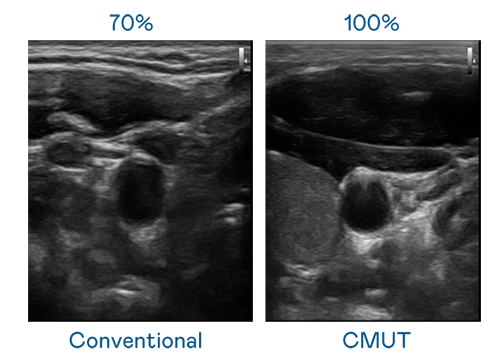

CMUT 技術是一種用電容式微機電元件來產生超音波訊號的技術。與傳統 PZT 壓電式技術相比,CMUT 頻寬增加 30%,更寬頻的超音波訊號讓影像解析度大幅提升,是實現高影像品質醫療超音波掃描、促進精準醫療發展的關鍵技術。

超音波影像的解析度高低,首先取決於探頭能發出的訊號頻寬。wepoker微扑克 CMUT 可提供高清晰的超音波訊號,提供高頻寬、高靈敏度、影像紋理細節更高的超音波影像,協助醫護人員縮短影像判讀時間及利用精準的醫療影像進行診斷。